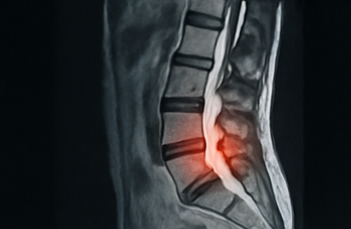

척추 뼈와 뼈 사이 있는 추간판이 돌출하거나 탈출해 신경을 압박하면 허리통증 원인으로 자주 지목됩니다. 디스크가 밀려 나가면 다리 저림, 감각 이상을 동반하기도 해요. 중년 이후에 특히 주의해야 하는 허리통증 원인이죠.

척추관 협착증

허리 속 신경이 지나는 통로가 좁아지는 상태가 척추관 협착증입니다. 허리통증 원인 중 이 질환은 특히 보행 시 통증이 심해지는 특징이 있어요. 오래 걷다 보면 다리가 무겁고 통증이 와서 멈췄다 다시 걷는 증상이 나타납니다.